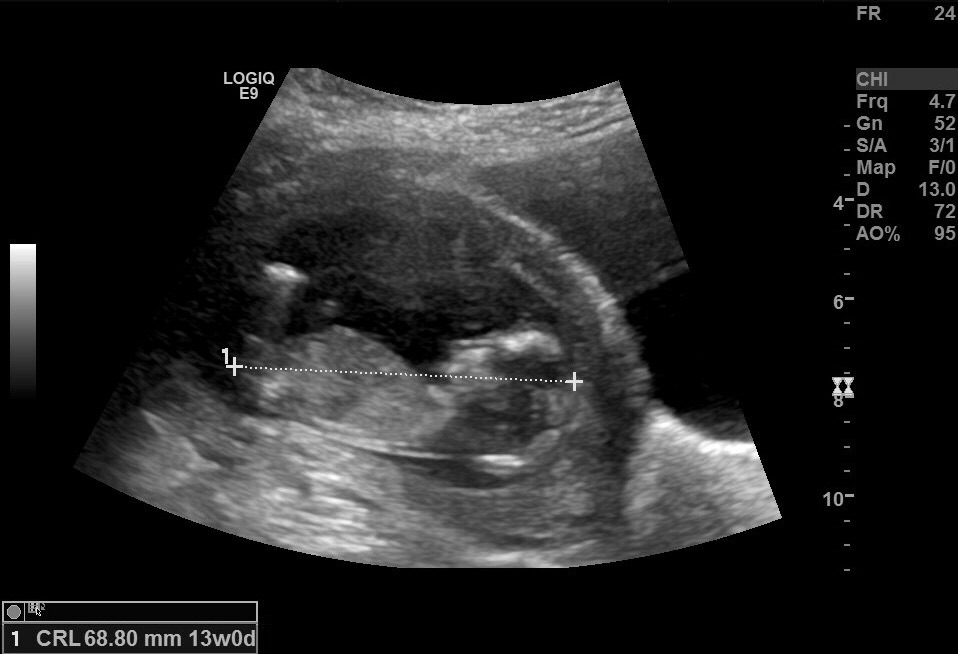

Hey everyone.. I had a scan yesterday at exactly 13 weeks & I think I got some good pictures but I just can't tell if there is any significant angle so I'd love your help :)

I adjusted the pic a bit so that the babies back is flatter & there is a rise but it's definitely not more than 30 degrees. Probably about 20 degrees. I'm also unsure how accurate the potty shot is because I didn't ask the sonographer to take a pic, that's just the one she took of the legs :)